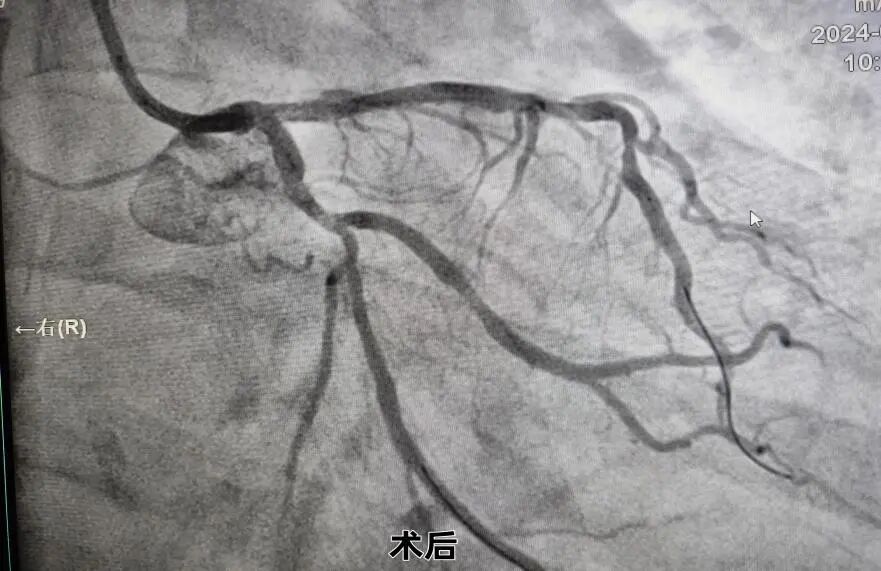

患者为65岁老年患者,因“反复胸痛20余天”入院,有高血压病史,有吸烟史。心电图:窦性心律,左心房扩大及左室肥大可能,入院后行冠脉造影检查:冠脉分布呈右优型;左冠及右冠走行区钙化影,左主干末端90%狭窄并累及前降支、回旋支开口,前降支开口-中段弥漫性狭窄,最窄90%,血流TIMI3级;回旋支开口80%狭窄,近-远段弥漫性狭窄,最窄75%,血流TIMI3级;右冠管壁欠规则,近段30%局限性狭窄,中段30%局限性狭窄,远段90%管状狭窄,后降支开口-近段50%局限性狭窄,中段50%局限性狭窄,血流TIMI3级。

面对如此复杂高危的冠脉病变,制定合理的治疗策略非常关键,患者造影结束安返病房。随后在中组部“组团式”帮扶专家游琼主任医师指导下,徐宗荣及杨力副主任医师介入团队逐帧仔细判读冠脉造影结果,再次熟悉临床资料,认为该患者SYNTAX评分34分,遂建议首选外科搭桥手术,但患者与家属不同意外科手术并要求介入治疗。基于患者病情危重,病变复杂,介入手术难度极大,手术风险极高,需强支撑大管腔指引导管处理,介入团队综合考虑了患者病情及经济因素后,获得患者及其家属知情同意,决定迎难而上,经我院介入团队充分讨论及评估,利用桡动脉无鞘技术,采用IABP保护下采用SKS术式,成功植入4枚支架,手术总共耗时2个多小时,整个手术过程顺利,术中无并发症,患者术后恢复良好,胸闷痛基本缓解,目前患者已康复出院。